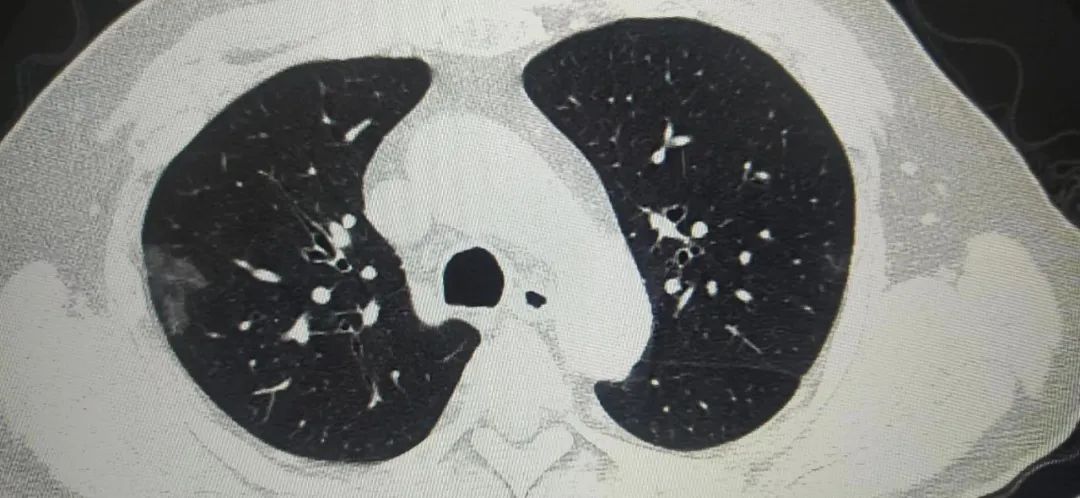

胸片只能做一个初步的粗略判断,付建英介绍,胸部CT则以1毫米为一层的断面,精准展现患者的肺部影像,就连软组织、骨骼场都能看得一清二楚,细微病灶也不会漏诊。在高分辨率的大尺寸屏幕上分析患者CT,即使是较小的磨玻璃样结节,都逃不过胸部CT的慧眼。

据陕西冶金医院医学影像科付建英主任讲,目前新闻各种报道奥密克戎感染后大部分为无症状或轻症,我自己接诊的患者中一部分有出现肺部表现的患者。比如上面的病例,CT检查都是出现了肺部表现,一个人是病变局限,病变于胸膜下分布。表现为单发或多发磨玻璃样密度结节状、斑片状影。其内可见空气支气管征和血管增粗表现。另外一个则是弥漫性磨玻璃样渗出,病变进展,病灶增多、范围扩大。可累及多个肺叶,下叶居多。病灶变密实。严格意义上讲,这几个病例都倾向于类似于新冠感染后的肺部表现。随着感染人数增多,可能还会有类似的病例出现。好在这样的病例确实不多,大部分还是上呼吸道感染的症状居多,发热咽痛是最常见的症状表现,但如果出现呼吸困难,还是要到医院拍个CT的。